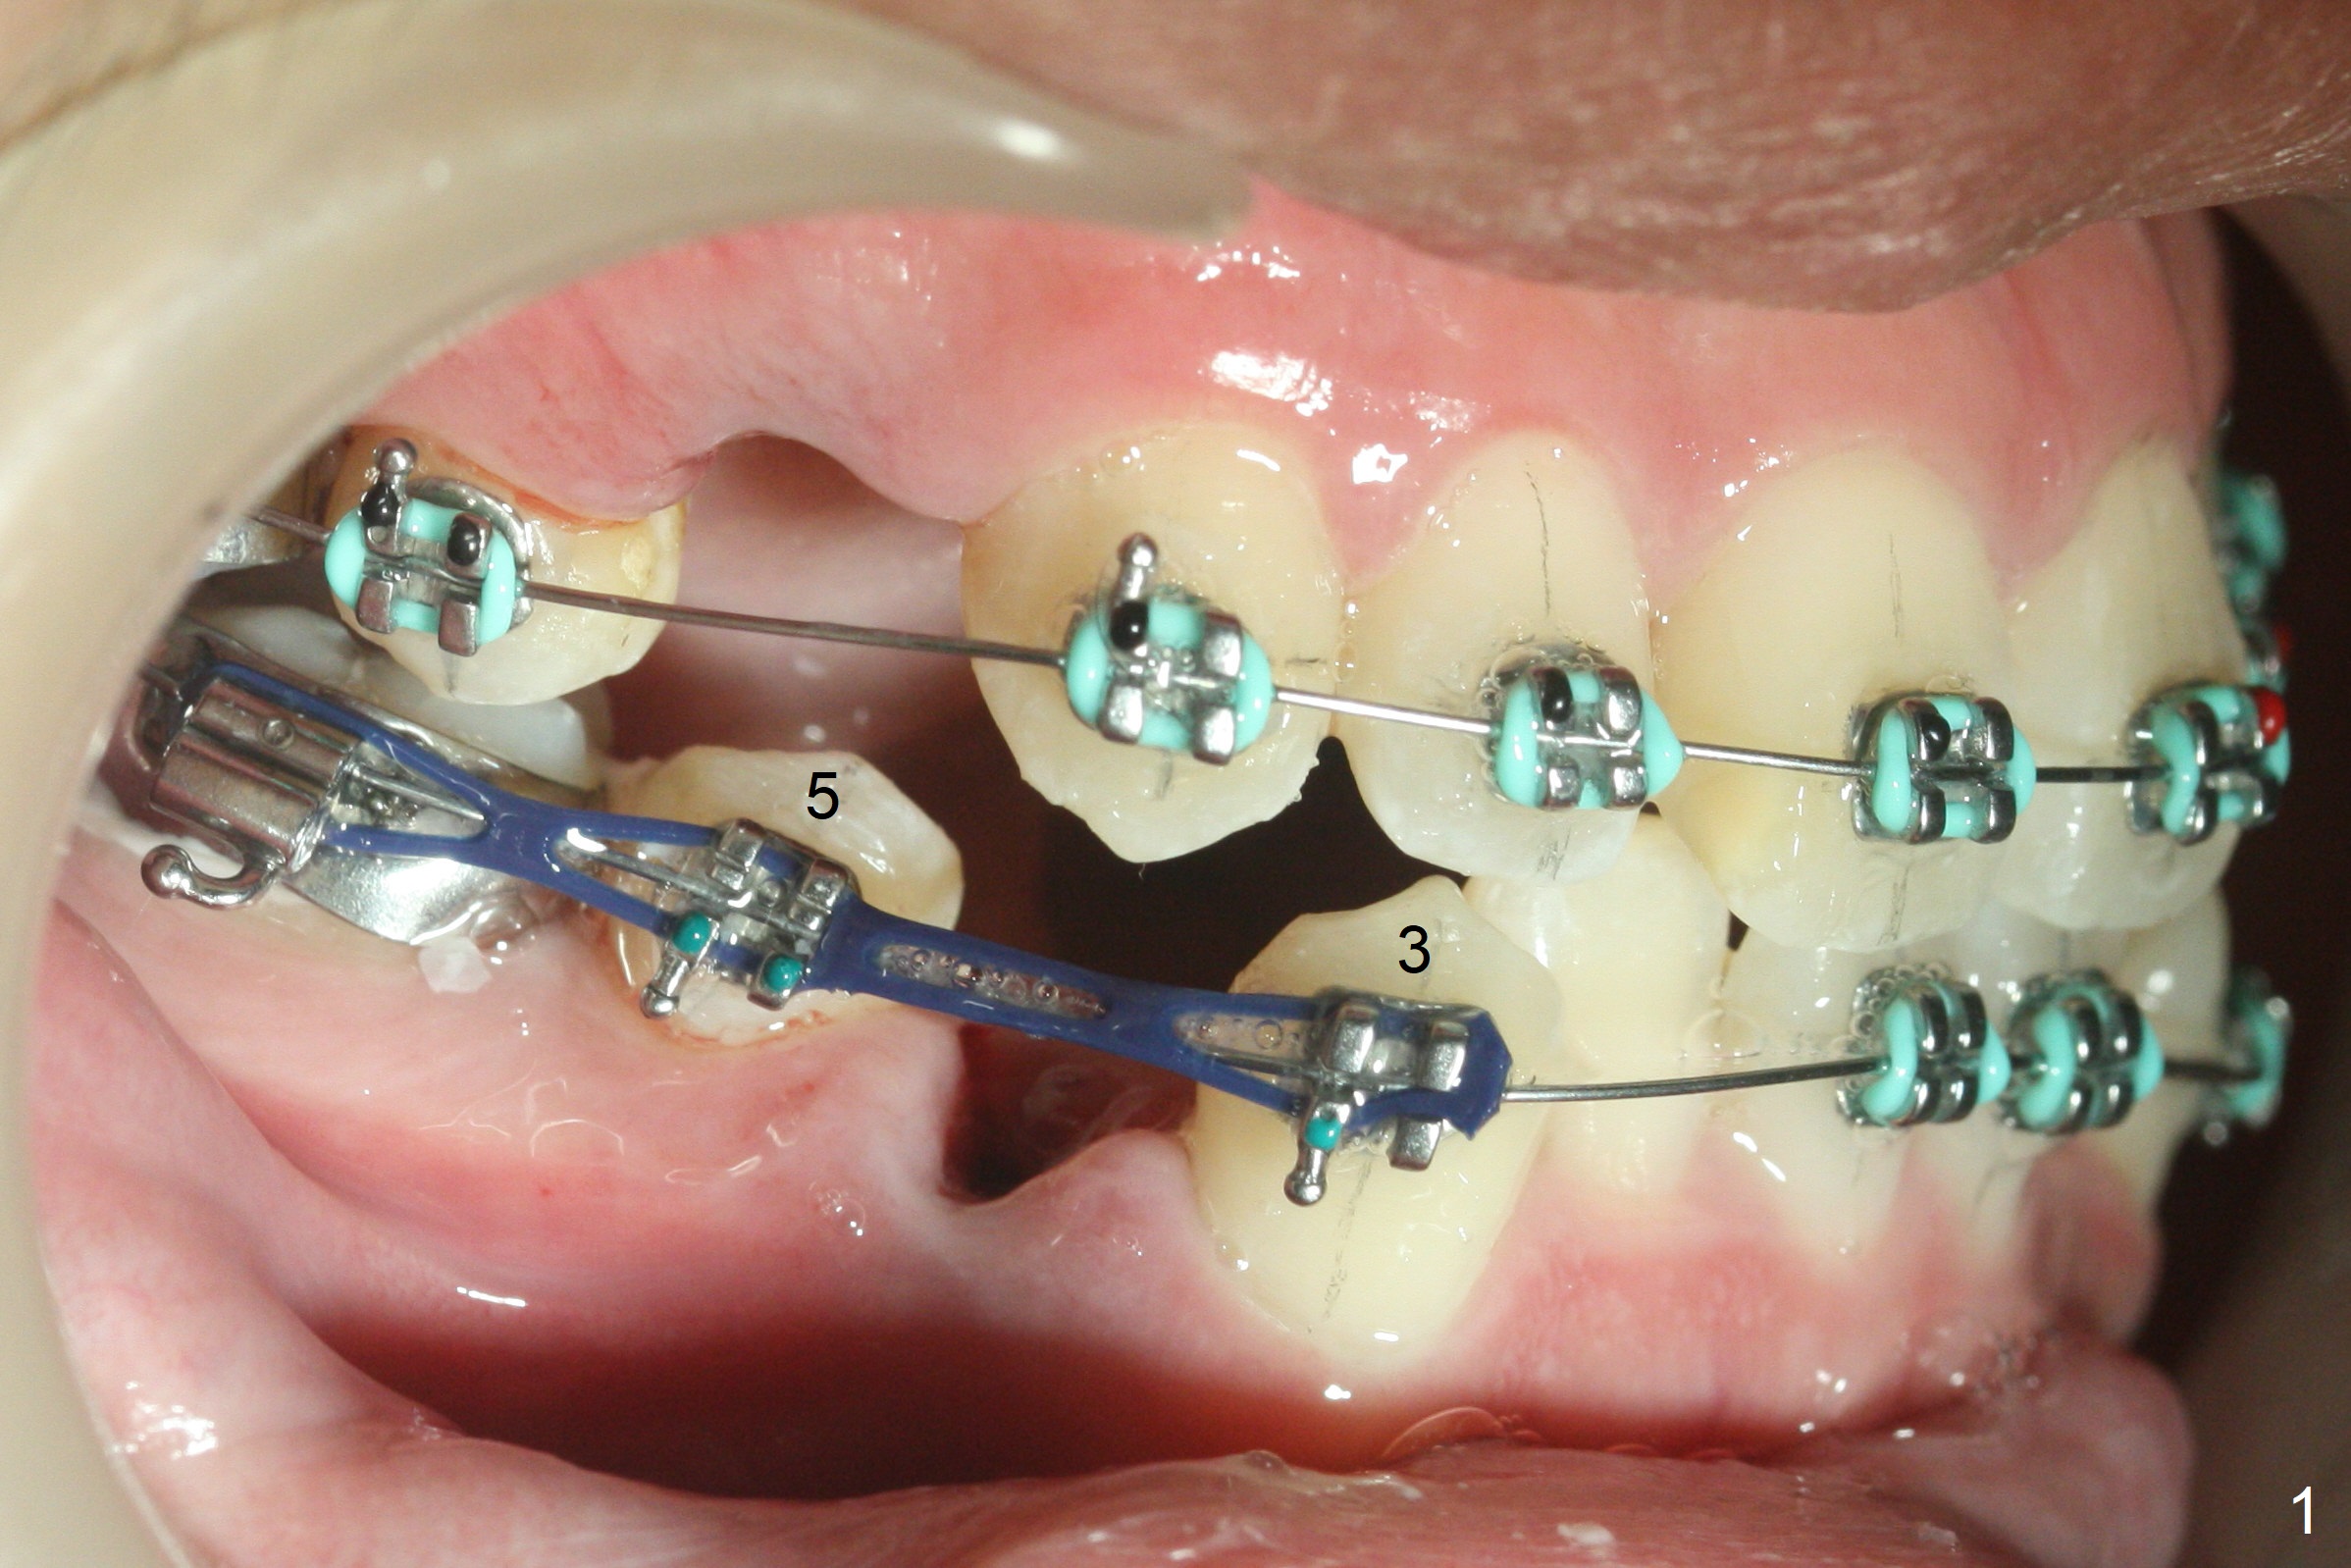

Four days post extraction of 4 of the 1st bicuspids, the patient returns for bracketing. It appears easier to place molar bands post extraction than without extraction. Spaces are larger. Anterior open bite (Fig.1-3) is due to premature contact of the mesiobuccal cusp of UR7 and the buccal tube at LR 7. To facilitate LR3 distalization, power chains are placed between LR3 and 6 (Fig.1 .014 niti wires), while tension in LL seems to be too high for power chains (Fig.3). The lower wire dislodges from the 2nd molar bands twice in 2 weeks; it appears that LR3 has been distalized (Fig.4); to reduce the chance of wire displacement, power chains x 5 are to be placed in LL 3-7 as well.

Plans: Next visit, do not necessarily change the lower wire so that it is easier to engage the wire to L2s' brackets once spaces arise. Use full arch power chains when L3s complete distalization.